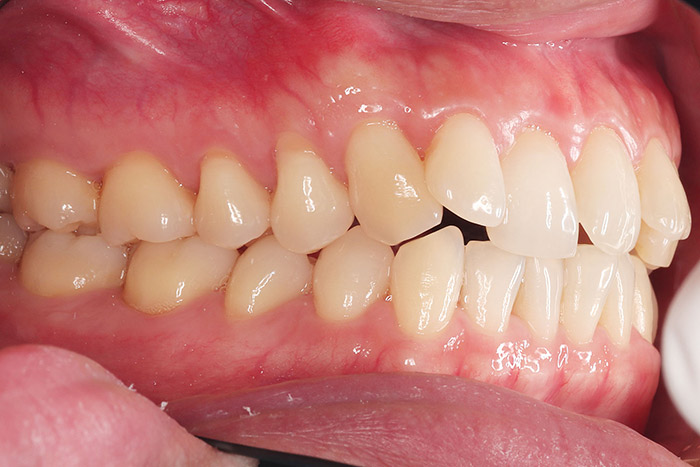

after

年齢 27歳

性別 女性

治療名称 マウスピース型カスタムメイド矯正歯科装置(インビザライン)・コンプリヘンシブパッケージ(フルパッケージ)

総額治療費用 770,000円(税込10%) 金額備考 精密検査料・診断料 33,000円(税込10%)

治療期間 1年11か月 通院頻度など 40日ごと

その他治療に関する情報

1枚につき10日装着を指示しました。

治療内容

患者の症状 上顎前歯の前突、八重歯

治療方法 上下左右の第一小臼歯抜歯で、マウスピース型カスタムメイド矯正歯科装置による矯正

治療結果 上顎前歯の前突、八重歯が改善されました。

歯並びをより良くするために追加でアライナーを発注しました。

治療を行う上での注意点

リスク/副作用 決められた時間装着する必要があります。